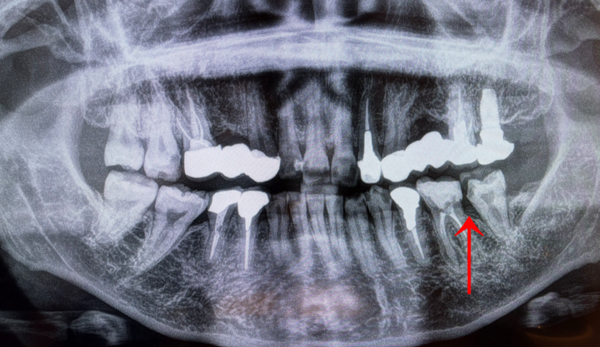

レントゲン検査(二次元画像)と歯周ポケットの測定により、左下の一番奥歯の周りの骨が溶けていることが分かりました。

さらに詳細を確認するためにCT撮影を行ったところ、左下の一番奥歯とその手前の歯の間の骨が部分的に溶けていました。

噛み合っている上の歯には、10年以上前に他院で埋入されたインプラントが装着されていました。